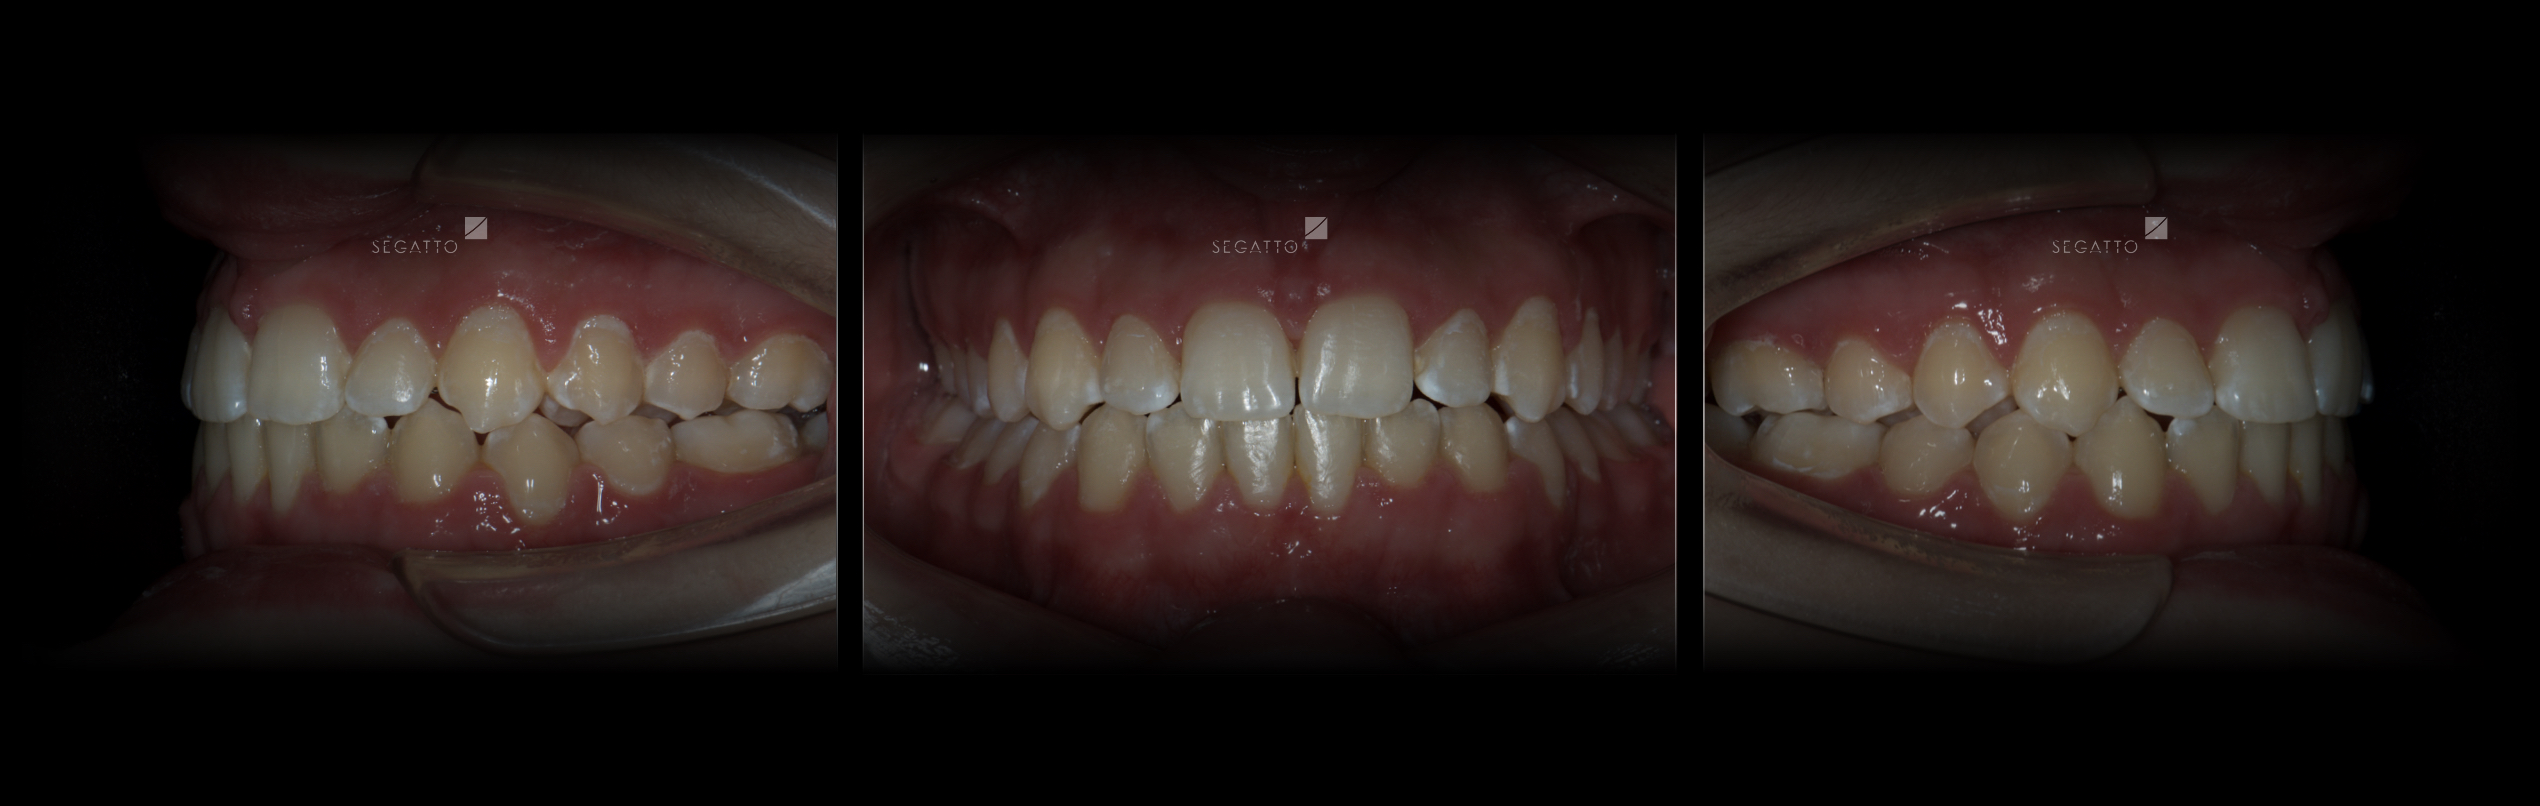

Orthodontics

Cases